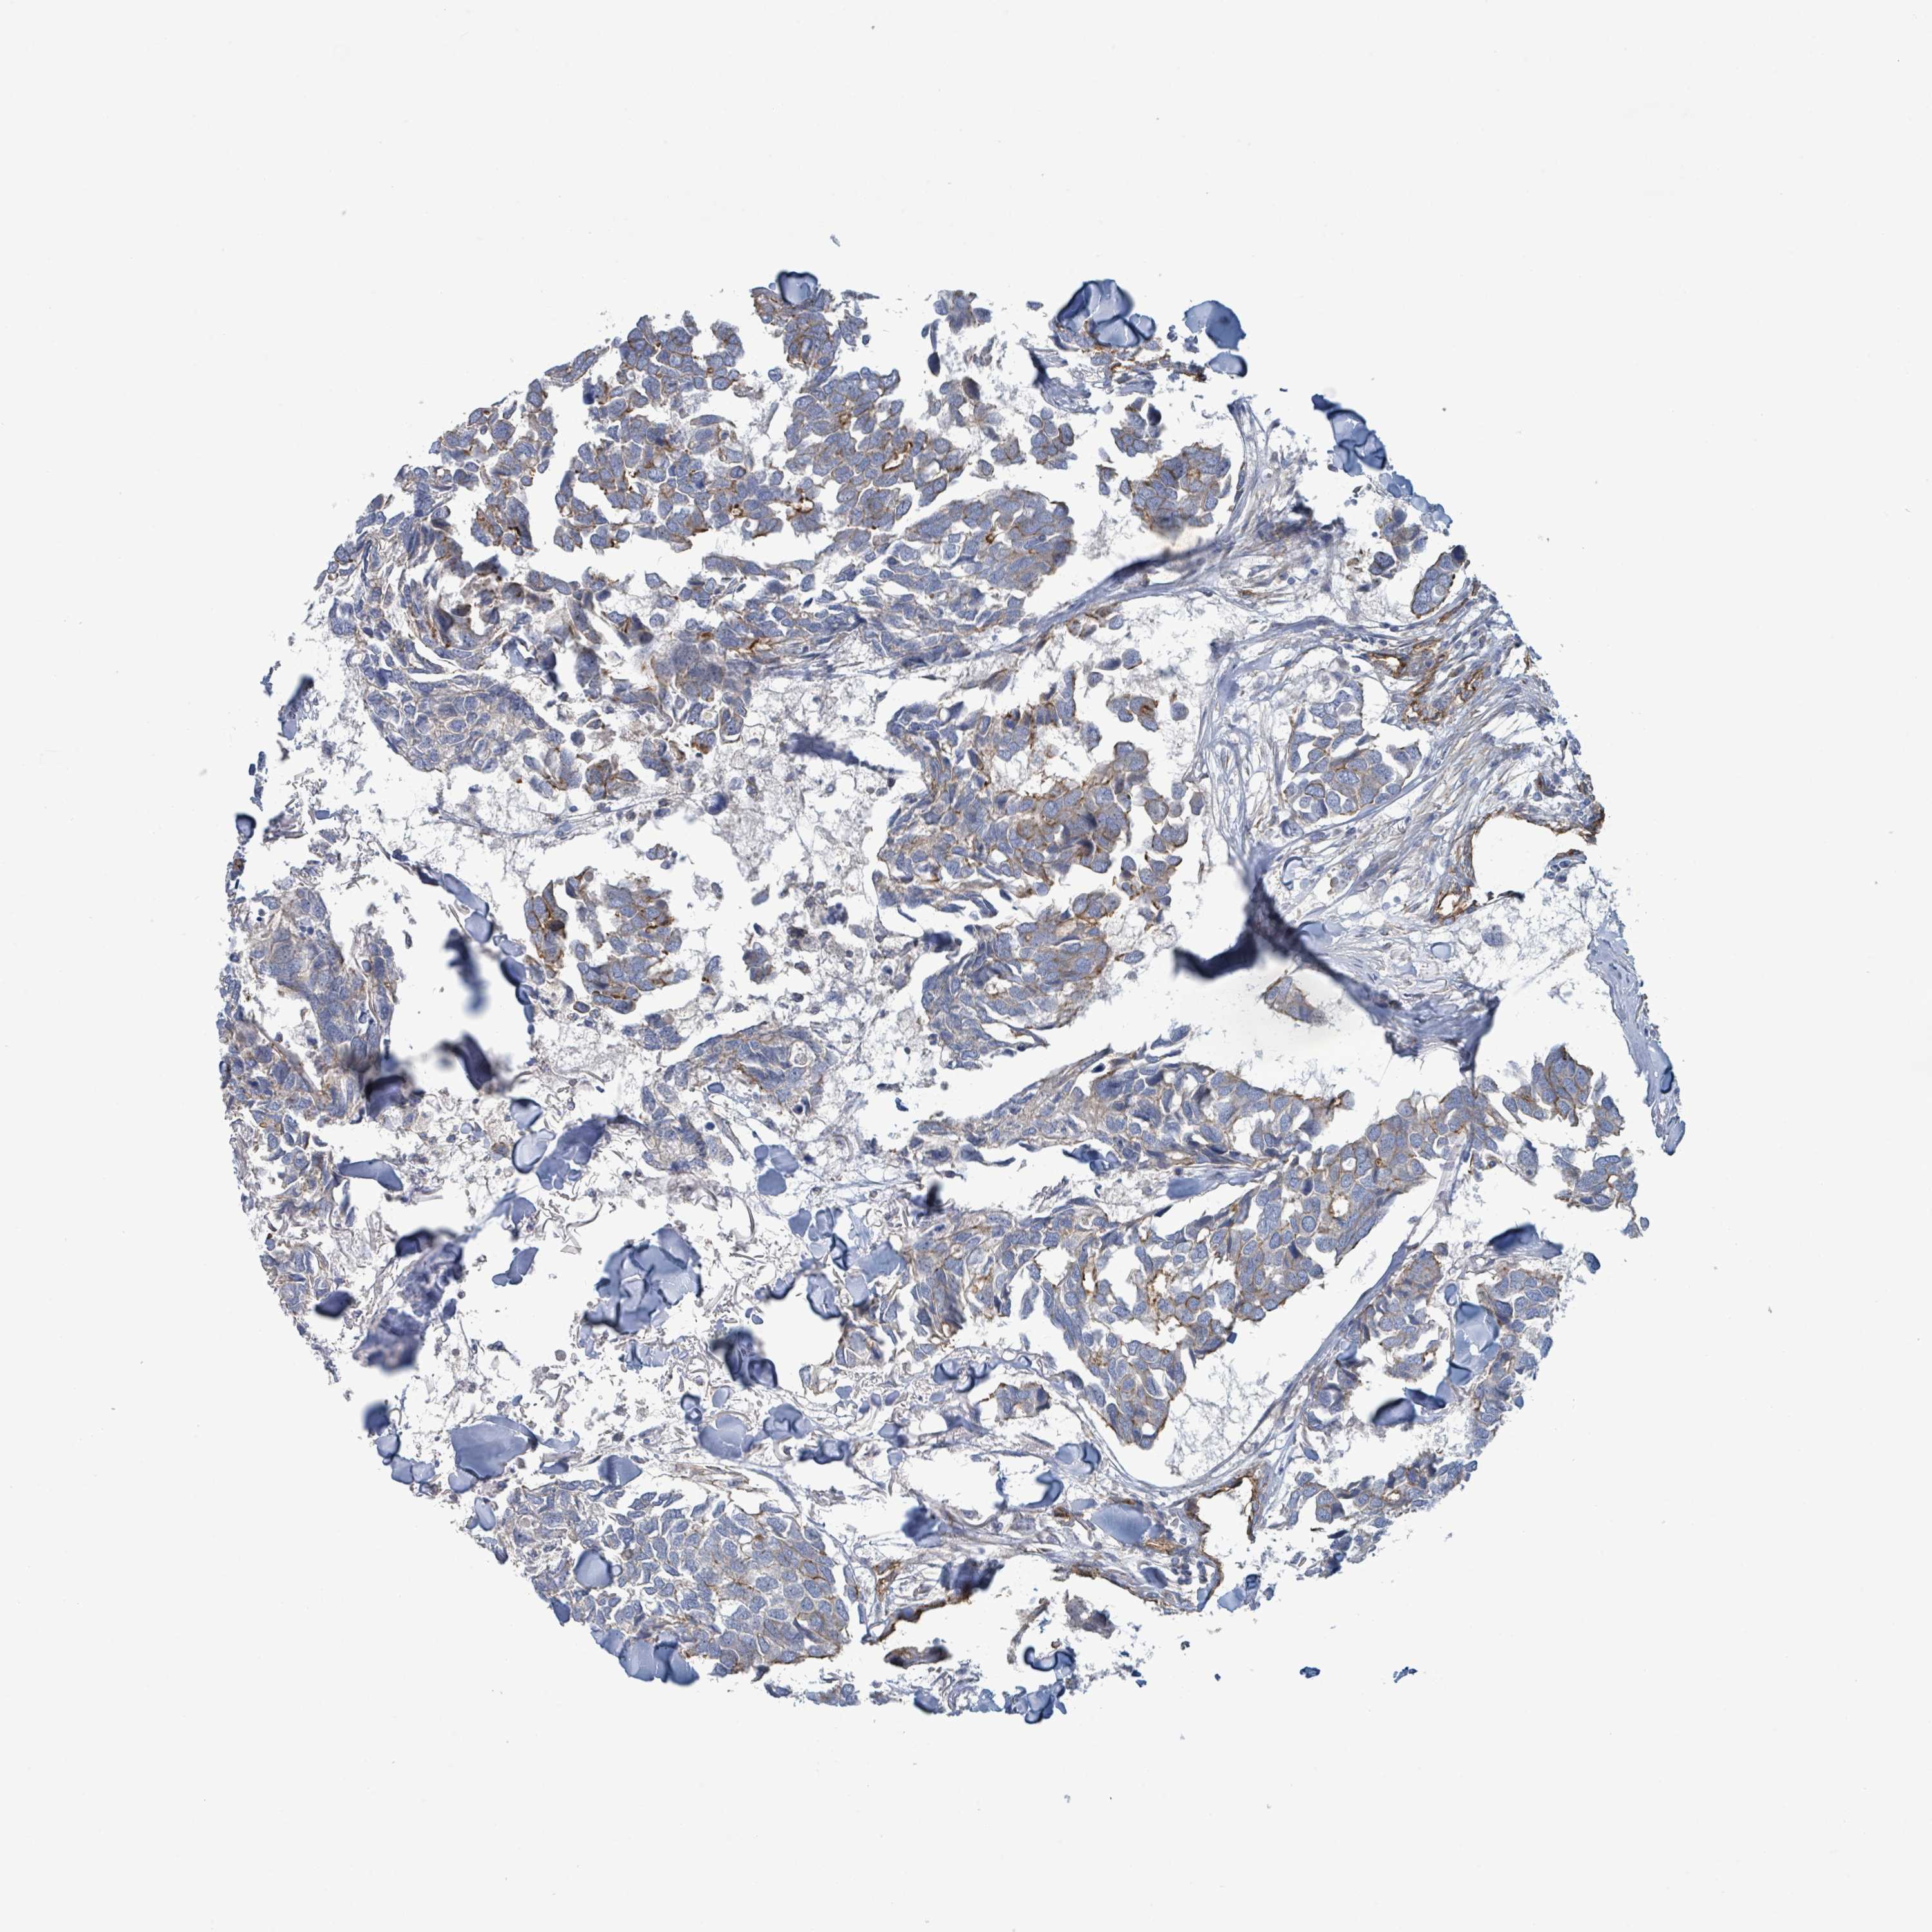

CANCER BREAST CANCER Show tissue menu

BRCA TCGA BRCA VALIDATION PROTEIN EXPRESSION